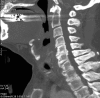

Pathologic fractures involving the C2 vertebral body and odontoid process pose a unique dilemma, as the surgical approach for direct odontoid process screw fixation has several limitations. There have been a small number of transoral approach C2 vertebroplasty or kyphoplasty reported in the literature. Previous attempts were performed utilizing fluoroscopy or CT guidance. We report a case of a fluoroscopically guided transor-al approach vertebroplasty in a patient with a lytic lesion involving the C2 vertebral body, extending into the odontoid process with an underlying pathologic fracture. This case is unique as two separate punctures were required in order to adequately stabilize the pathologic fracture, CTA was performed preoperatively to better evaluate regional vasculature, and a post-procedure rotational flat panel CT was performed to assess cement placement.